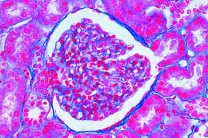

- Mikroskopie